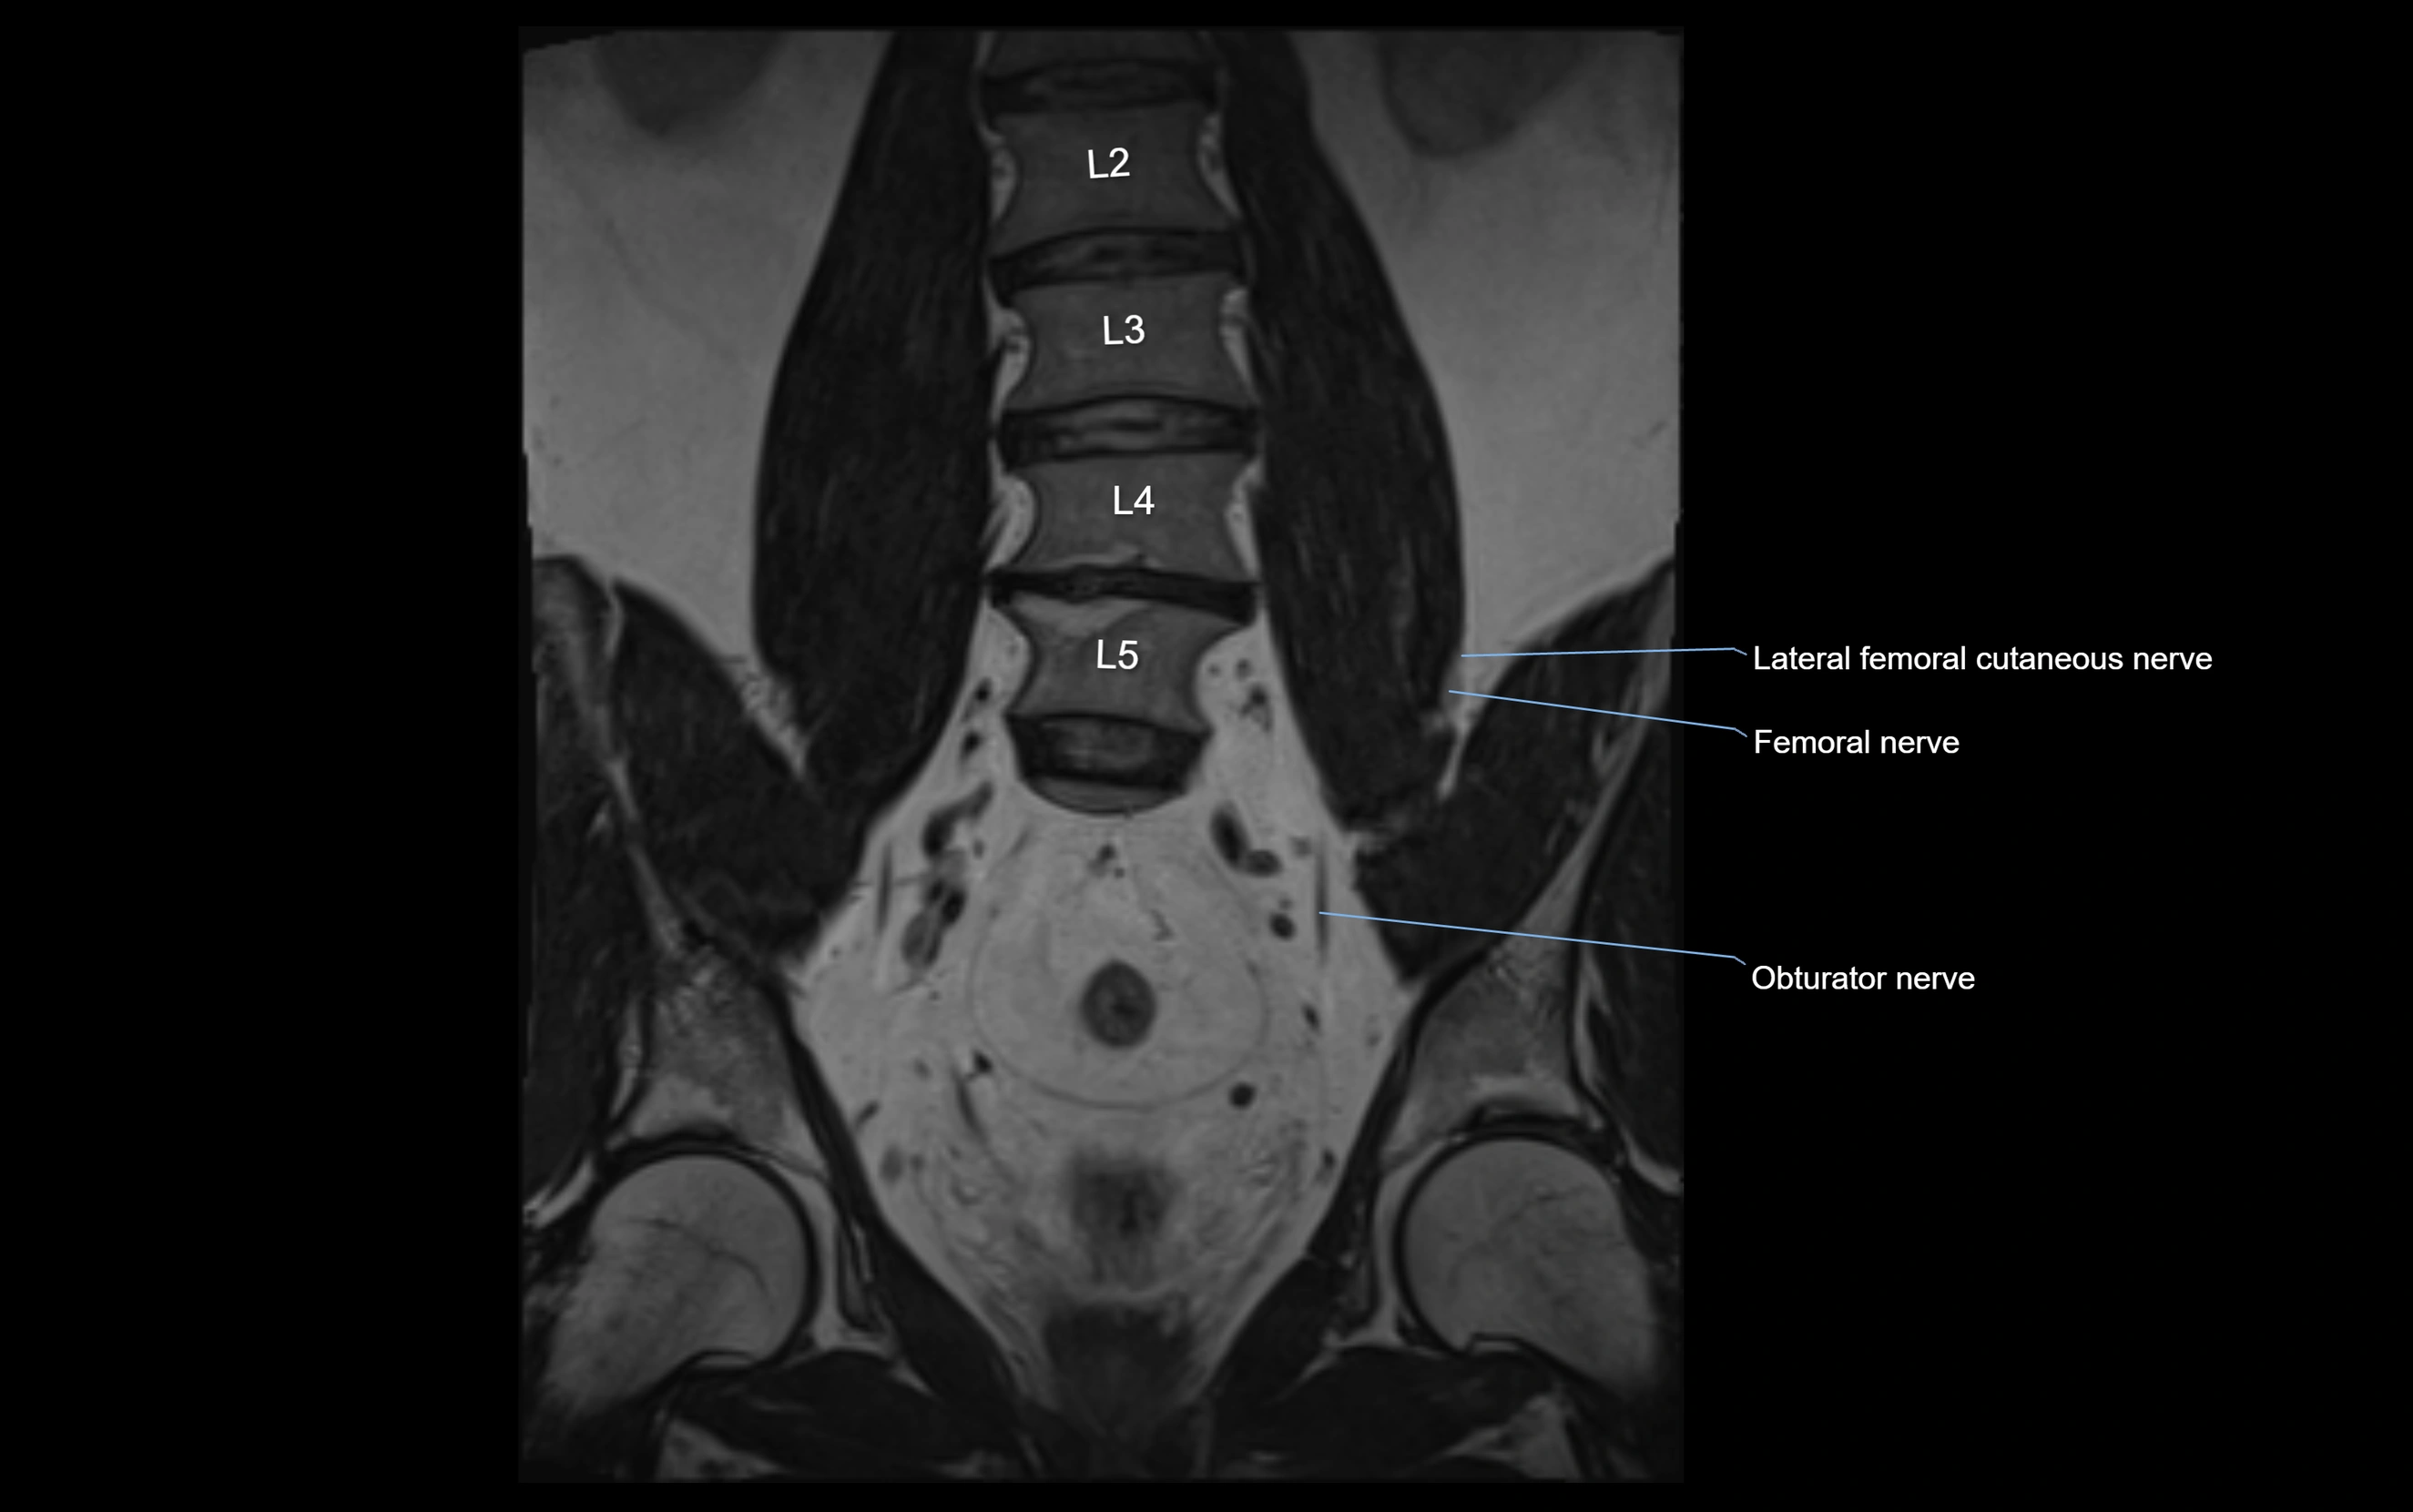

MRI image

image